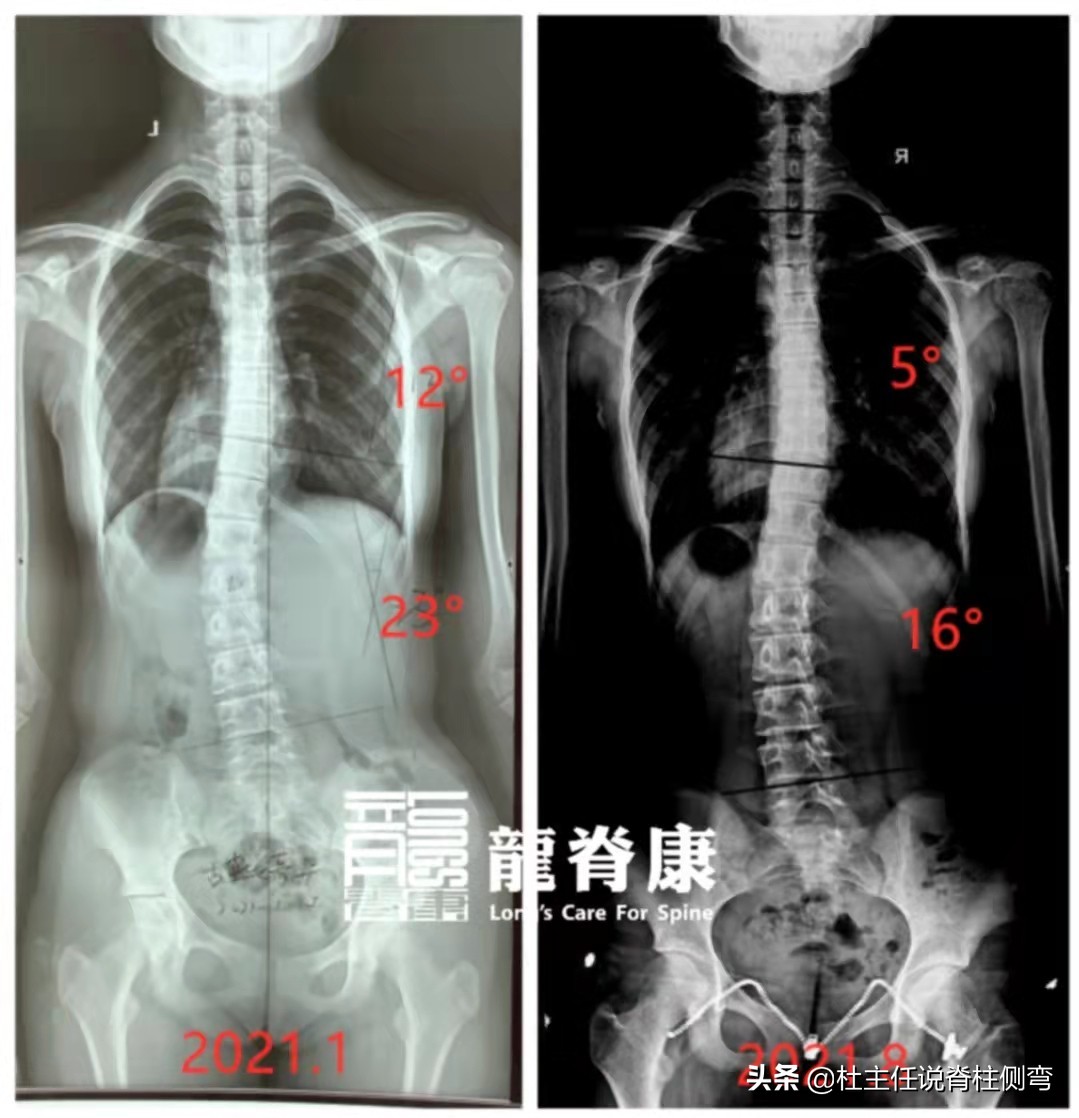

今年11岁的小林,在2021年1月份时,家长发现其骨盆有一高一低,在陪同孩子洗头发时又发现弯腰下肌肉一边高一边低,随后立即去当地医院拍片,侧弯度数为23°。

后来经朋友的推荐,来到了龙脊康门诊接受7D疗法治疗,孩子每天坚持佩戴GBW支具,9月份脱支具下拍片复查:胸弯度数从12°减到5°,腰弯度数从23°减到16°,身体中线也基本回归,从体表看上去很对称。

经过长达8个月的戴支具和体操训练,剃刀背从原来的14°下降至现在的4°。而一个正常的成年人的剃刀背正常值在5°以内,所以孩子现在的体表已经是属于正常水平了。